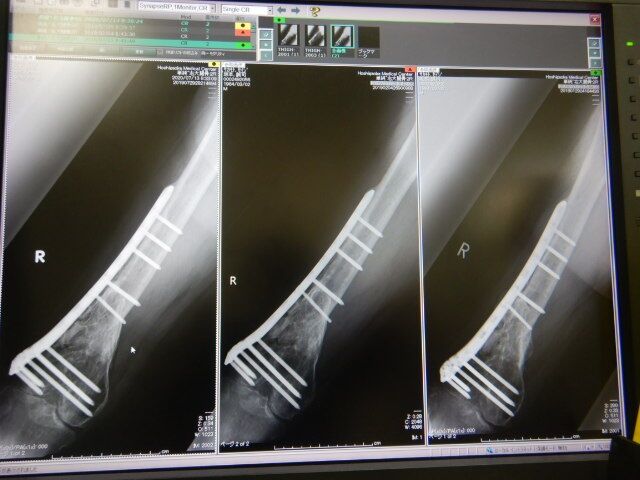

±¦Âǯ¼¡ÅÀ¸¡¤Ø¹Ô¤Ã¤Æ¤¤Þ¤·¤¿¡£±¦²èÁü¤«¤é2018ǯ¡¢2019ǯ¤È¤Ê¤ê

º¸¤Î¥ì¥ó¥È¥²¥ó²èÁü¤¬2020ǯº£Æü¤Î

±¦Â¤Î¥ì¥ó¥È¥²¥ó²èÁü¤Ë¤Ê¤ê¤Þ¤¹¡£